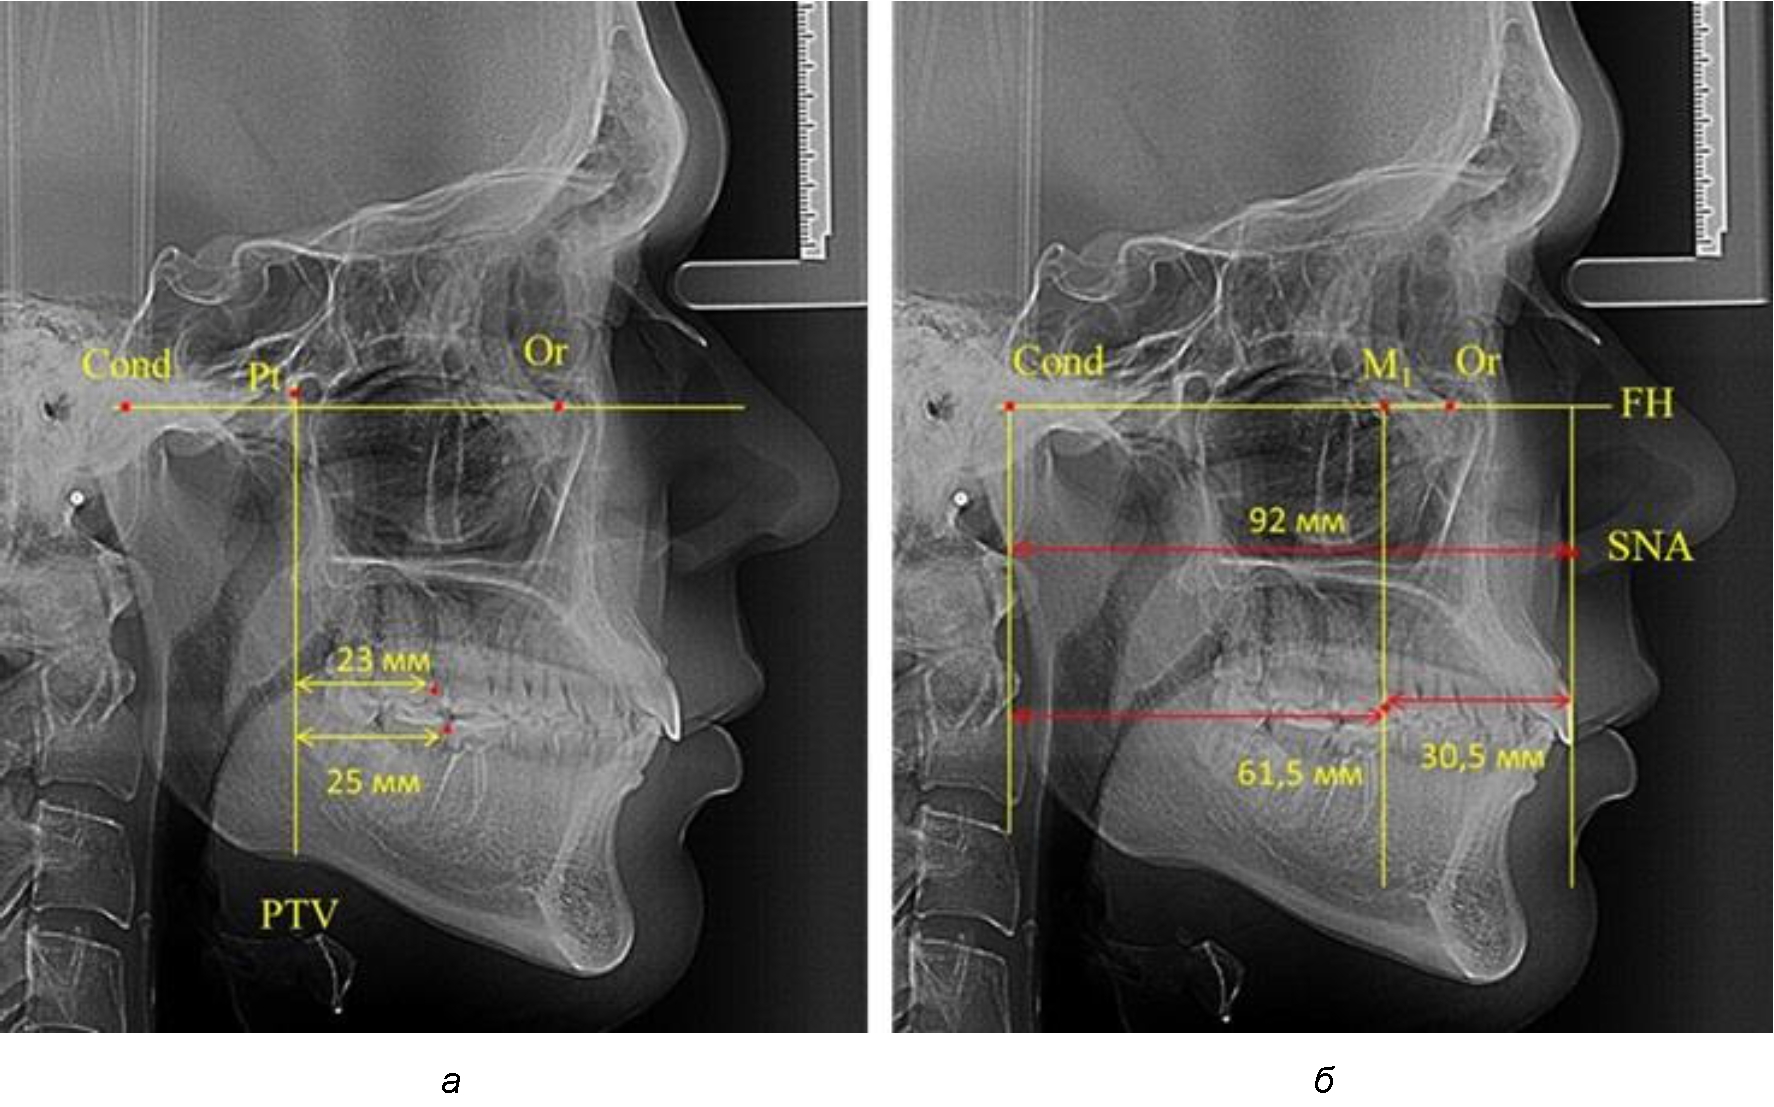

При проведении анализа к Франкфуртской горизонтали проводили передний и задний перпендикуляры. Передний спинальный перпендикуляр проходил через выступающую точку передней носовой ости (spina nasalis anterior – SNA), а задний суставной перпендикуляр опускали из кондилярной точки Cond. Молярный перпендикуляр проводили через медиальную поверхность первого постоянного моляра. Указанная вертикаль отделяла замещающие зубы постоянного прикуса от добавочных зубов (постоянных моляров), что вполне логично для анализа положения первых постоянных моляров в гнатическом комплексе (рис. 1).

Рис. 1. Метод определения положения первых верхних моляров по Ralph E. McDonald (а) и по предложенному методу (б)

Анализ проведенного исследования рентгенограмм показал существенную вариабельность практически всех линейных показателей. У молодых людей с физиологическим прикусом постоянных зубов расстояние от крыловидной вертикальной плоскости PTV до дистальной поверхности верхнего первого постоянного моляра в целом по группе составляло (18,37 ± 3,62) мм. Обращает на себя внимание большая ошибка репрезентативности из-за разницы между максимальными и минимальными значениями.

Среди анализируемых рентгенограмм минимальное значение расстояния по методу R. E. McDonald было 12 мм, а максимальное достигало 25 мм, что, по нашему мнению, обусловлено вариабельностью сагиттального размера гнатического отдела лица.

Так, при расстоянии от крыловидной вертикальной плоскости PTV до дистальной поверхности верхнего первого постоянного моляра в 13 мм сагиттальный размер гнатического отдела был 82 мм. При этом отношение кондилярно-спинального расстояния к кондилярно-молярному размеру (54,5) было близким к коэффициенту 1,5, что представлено на рис. 2.

В то же время при увеличенном расстоянии от крыловидной вертикальной плоскости PTV до дистальной поверхности верхнего первого постоянного моляра, равное 23 мм, сагиттальный размер гнатического отдела составил 92 мм. При этом отношение кондилярно-спинального расстояния к кондилярно-молярному размеру (30,5), так же, как и при малых размерах, было близким к коэффициенту 1,5, что представлено на рис. 3.